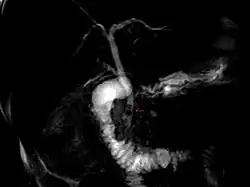

| Magnetic resonance cholangiopancreatography (MRCP) image of two gallstones in the distal common bile duct | |